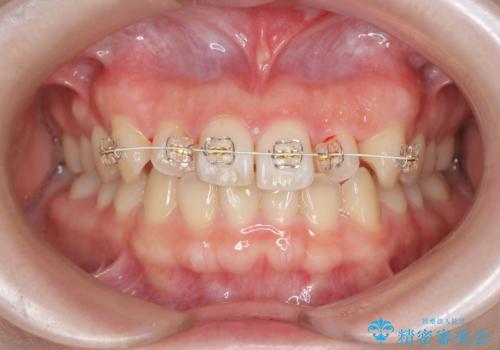

- 「前歯のねじれ、見た目を改善したい。」と矯正治療を希望され来院されました。

マウスピース矯正では改善の難しい前歯のねじれを前歯の部分ワイヤー矯正で改善したのち、インビザライン矯正を行い歯列を整えます。

インビザラインを行う前に前歯の部分矯正を行ったことで、しっかりとねじれが取れ整った歯列へと仕上げることが出来ました。